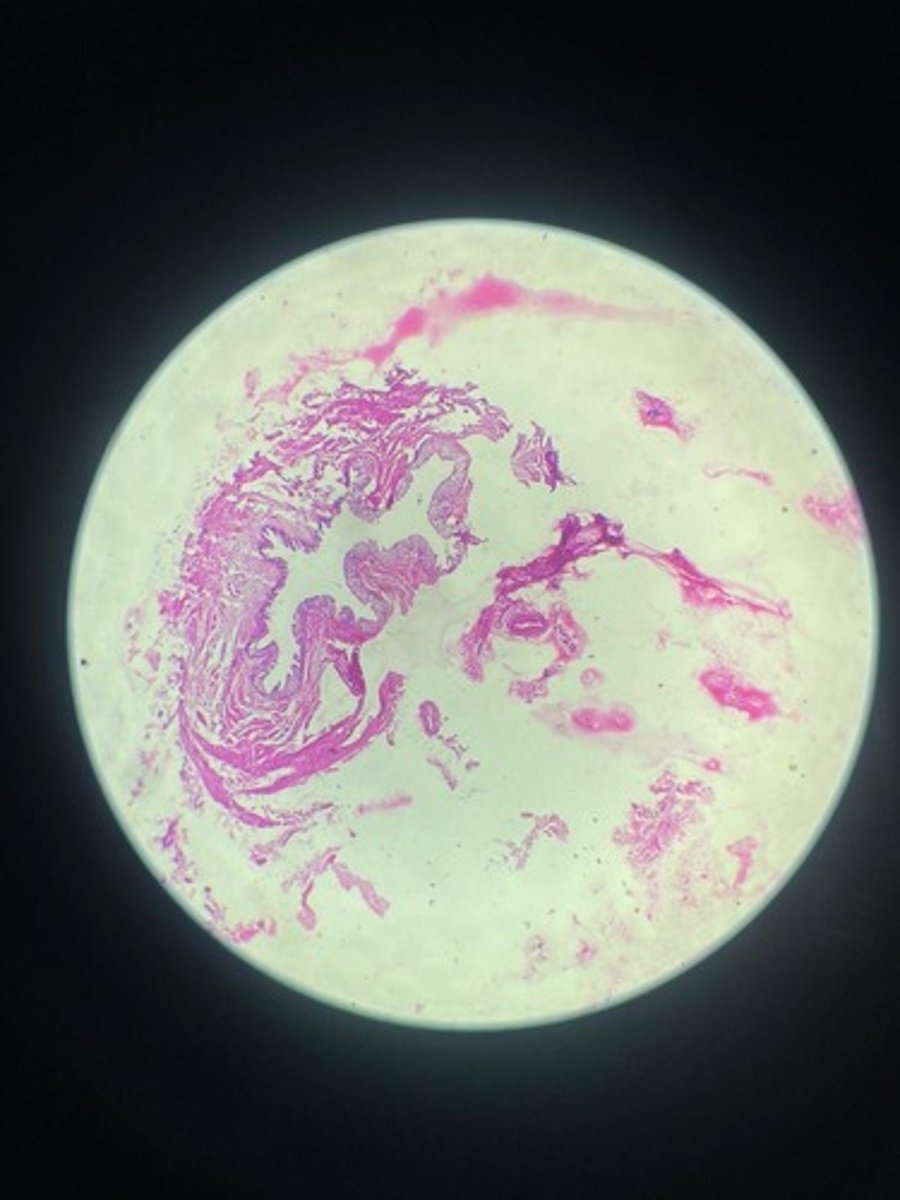

Ureter HE

Ureter HE

Ureter HE

Ureter HE

Ureter HE